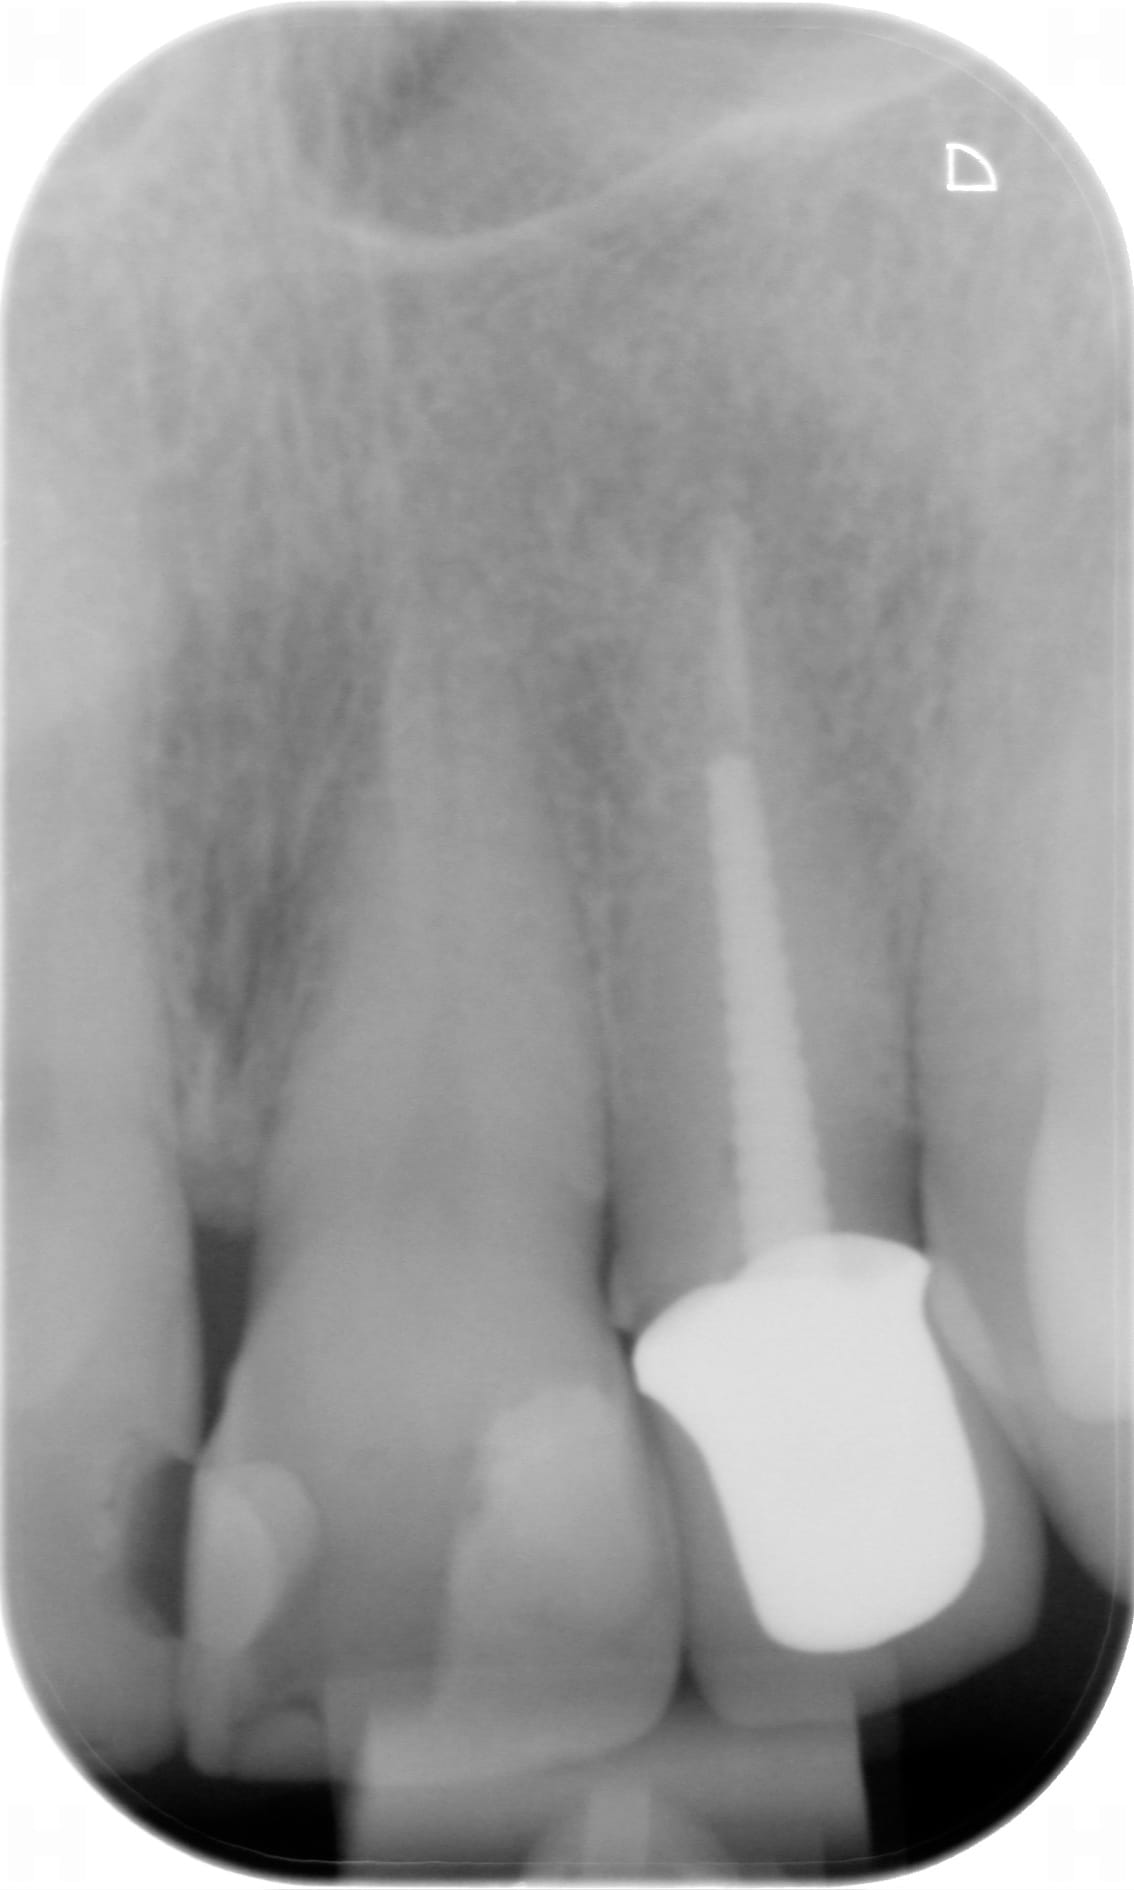

Je viens de déposer un compo sur une PM2 avec traitement endo depuis 10 ans.

Il me semble apercevoir une fissure en M .

R: il y a une fistule qui aboutit ,en mettant un cone de gutta + RX ,en M de la racine (et pas du tout à l'apex)

Marrant parce que cette fêlure sur 22, on ne la voit pas du tout sur la rétro, mais très bien sur la reconstruction 3D du CBCT

Jwjbelah9gpo9q1h8cqdm9j3kbi5 - Eugenol